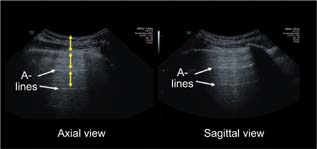

A-lines (Figure 4): these appear as motionless and regularly spaced horizontal lines under the pleural line. These correspond to normal reverberation artefact of the pleural line. A-lines and lung sliding define normal aeration.62

FIG 4. A-lines.